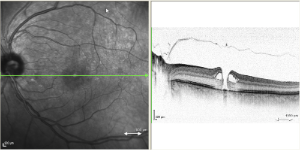

The macula is the part of the retina responsible for central vision, the vision one uses for reading, watching television, and recognizing faces. A macular hole is a small round opening in the macula. The hole causes a blind spot or blurred area directly in the center of your vision.